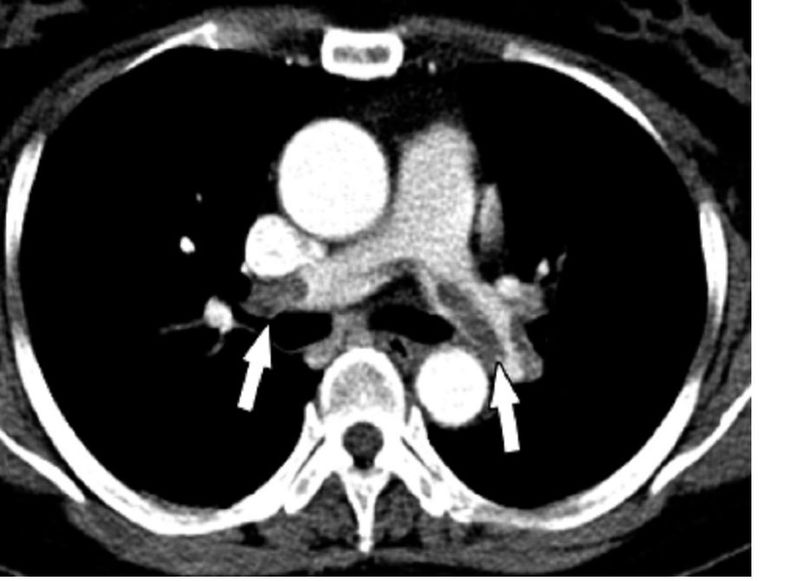

특히 폐 전산화 단층 촬영(CT)은 폐 색전증을 진단하는 데 가장 유용한 검사인데, 폐 혈관을 막고 있는 혈전을 확인함으로써 진단할 수 있습니다. 요즘에는 해상도도 좋아지고 있고 CT 혈관 조영술의 기법도 있어서 더 작은 혈전을 발견할 수 있습니다.

폐 색전증 환자의 CT 이미지 (출처 : 위키 미디어)